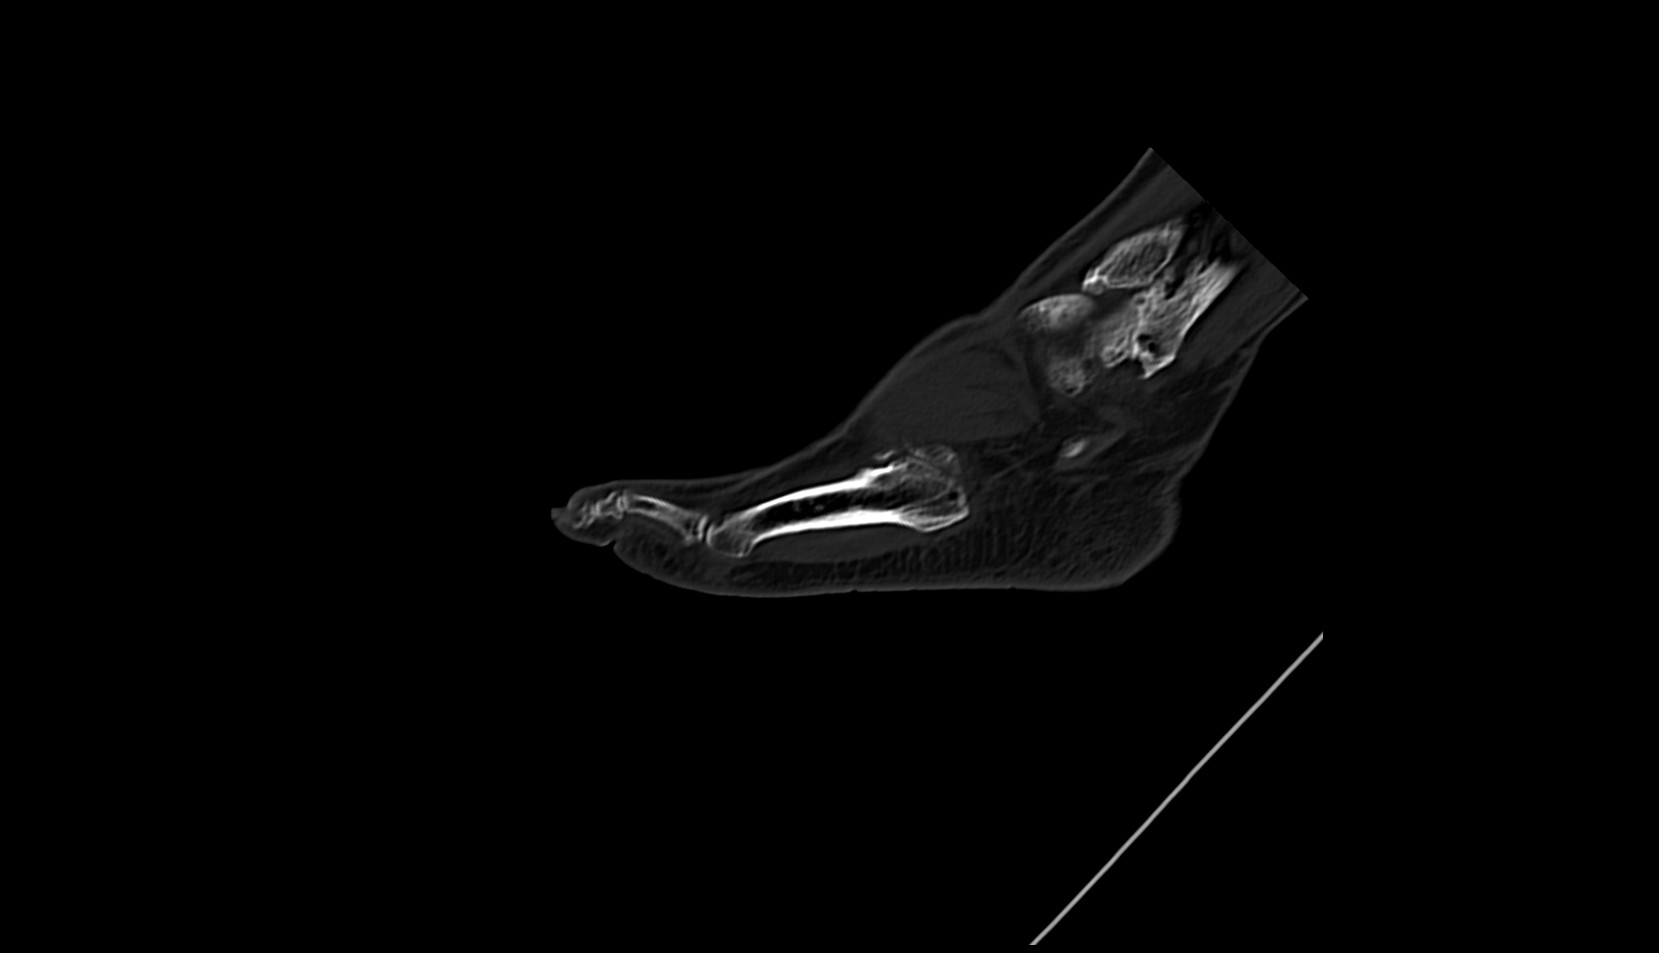

- Talus

- Calcaneus

- Achilles tendon